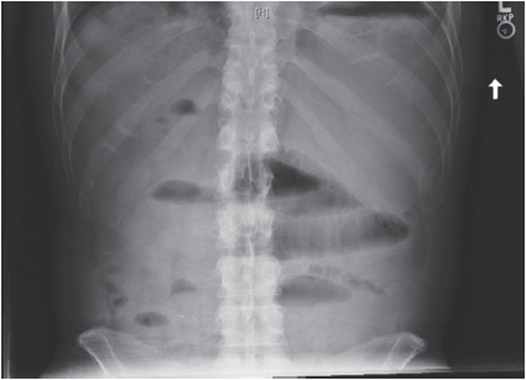

Next, assess the patient’s vital signs and then examine the patient. Abdominal distension is frequently present in ileus and small bowel obstruction. Hypoactive or absent bowel sounds are characteristic of ileus on auscultation of the abdomen, whereas hyperactive bowel sounds are more likely in obstruction. Abdominal plain films will show global dilation of small and large bowel in the case of an ileus (see Figure 38-1). An obstruction, on the other hand, will have proximally dilated loops of bowel, with distal decompression and paucity of air in the colon or rectum (see Figure 38-2).

Figure 38-1. Postoperative ileus: radiograph from a patient with postoperative ileus shows gastric distention, distended small bowel loops, and air and stool throughout the colon.